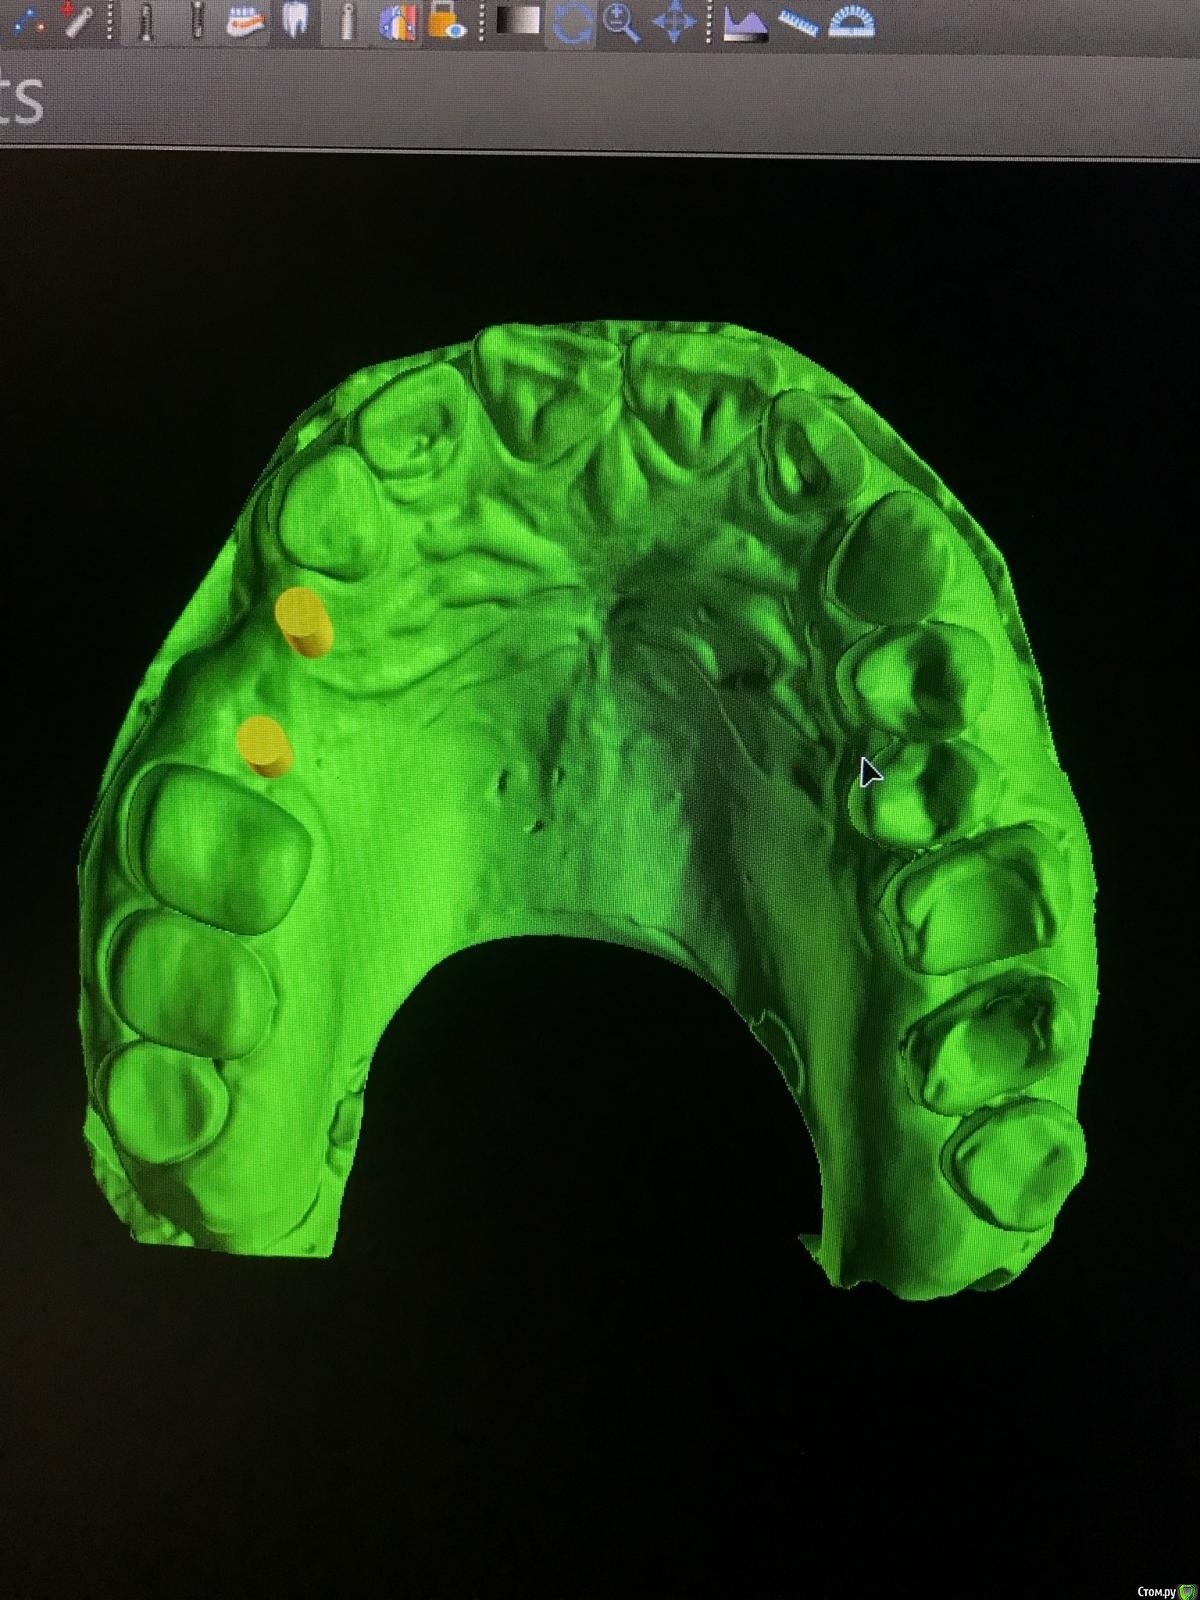

Женька Опубликовано 14 февраля, 2021 Автор Поделиться Опубликовано 14 февраля, 2021 (изменено) @Irouil, не слишком ли нёбно? как считаете? И в случае такого позиционирования, стоит ли перекрывать эту вестибулярную ямку сст? (подставил зубы виртуальные и понял, что там сосочек надо формировать будет, потому нужно объём тканей создавать) Делаем шаблон под пилот И всё-таки хотелось бы от ортопедов услышать ответ, пожалуйста: Я правильно думаю, что правильное ортопедическое положение может быть и с вестибулярным наклоном, главное чтобы шахта не в сторону губы верхней смотрела?) (утрирую) Изменено 14 февраля, 2021 пользователем Женька Ссылка на комментарий

Fin Опубликовано 14 февраля, 2021 Поделиться Опубликовано 14 февраля, 2021 1.5 как то очень близко к зубу Ссылка на комментарий

Женька Опубликовано 14 февраля, 2021 Автор Поделиться Опубликовано 14 февраля, 2021 Ну, 1.5мм там есть... но согласен, кажется прям впритык Ссылка на комментарий